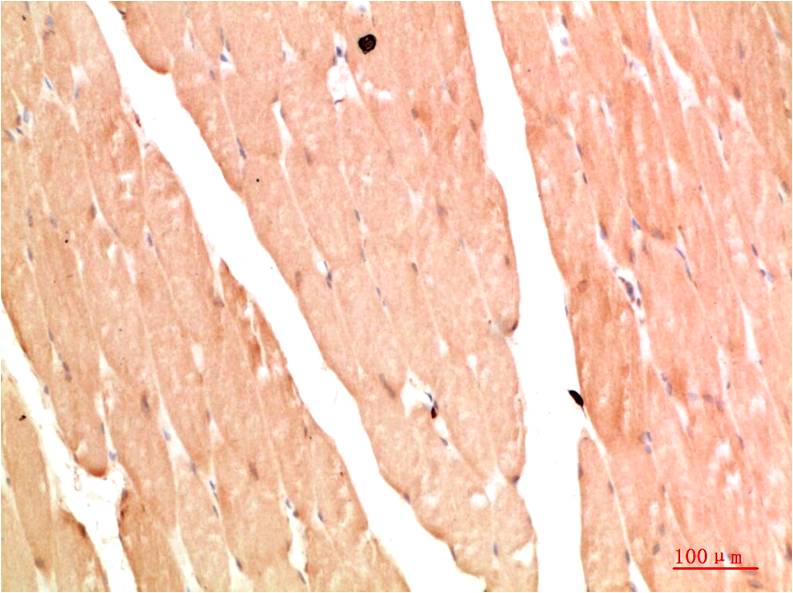

c-Jun Mouse Monoclonal Antibody(4G10)

Applications :IHC

| Recommended dilutions: | IHC 1:100-200 |

| Specificity: | The c-Jun Mouse Monoclonal Antibody can detects endogenous c-Jun proteins. |